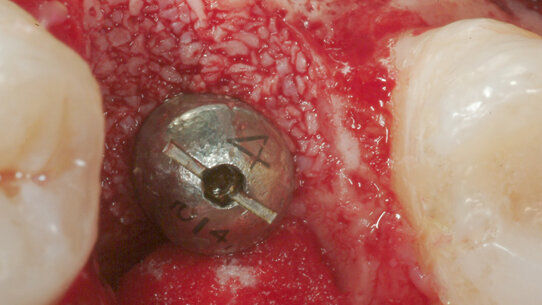

Pulito l’alveolo, è stato inserito un impianto di 5 mm di diametro di lunghezza 11,5 mm con una stabilità primaria superiore ai 30 Ncm.

Data la presenza di un difetto osseo vestibolare, è stato inserito un biomateriale come riempitivo del difetto (BIOSS) e una membrana in collagene a ricopertura dell’innesto (BIOGUIDE).